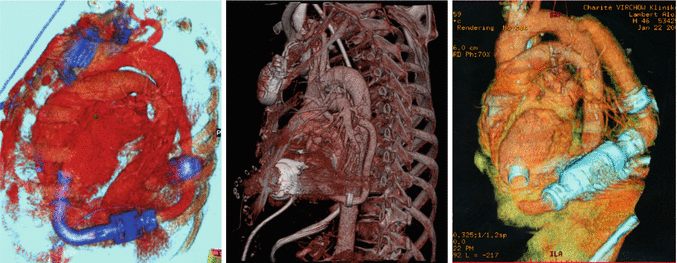

Fig. 27.2

Descending aorta outflow-graft placement by 3D computed tomography (CT) scan reconstruction